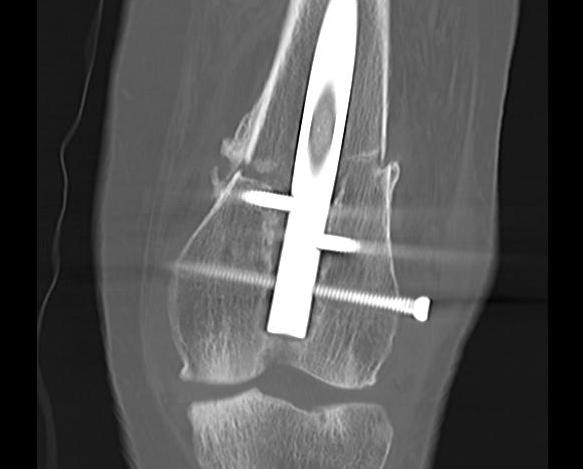

Type C: Complete articular

Xray / CT

Dual plate

Indications

Significant comminution

Loss of medial cortical buttress

Approach

1. Dual incision

- medial + lateral approach

- midlateral approach - split ITB, elevate vastus lateralis

- medial subvastus approach

AO surgery reference lateral approach distal femur

AO surgery reference medial approach distal femur

2. Single anterior incision

- extensile medial parapatellar approach

Vumedi extensile medial parapatellar approach